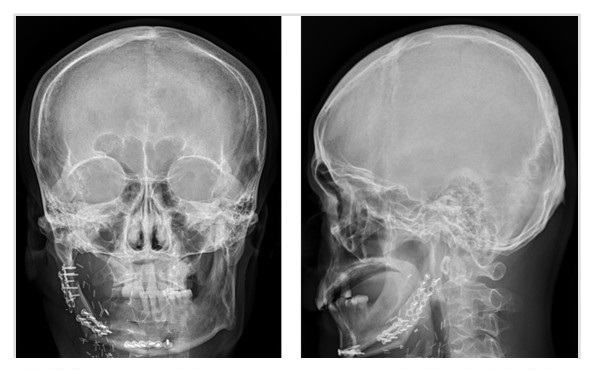

李建智副院長強調,幫病人回到癌症以前,「恢復舊觀甚至更好」,是整形美容醫學的最終使命。而「超音波抽脂微創複合術」就是目前體雕手術中重要的一環,除了減少腫脹加速恢復期外,微創治療更可以減少疤痕產生。李醫師進一步分析,超音波抽脂系統的原理,是利用震盪脂肪周圍的抽脂藥水的方式,鬆解疤痕,抽吸出乳糜化的脂肪,這項技術不僅僅可以使用在醫學美容體雕手術外,還可以應用在癌症術後外觀的修復,包括在乳癌義乳、乳癌自體皮瓣、及口腔癌重建手術後等,療效跟外觀皆明顯改善。除了癌症治療,抽脂體雕手術也可以運用在肥胖導致脂肪堆積,或是減肥後體態鬆弛的治療。